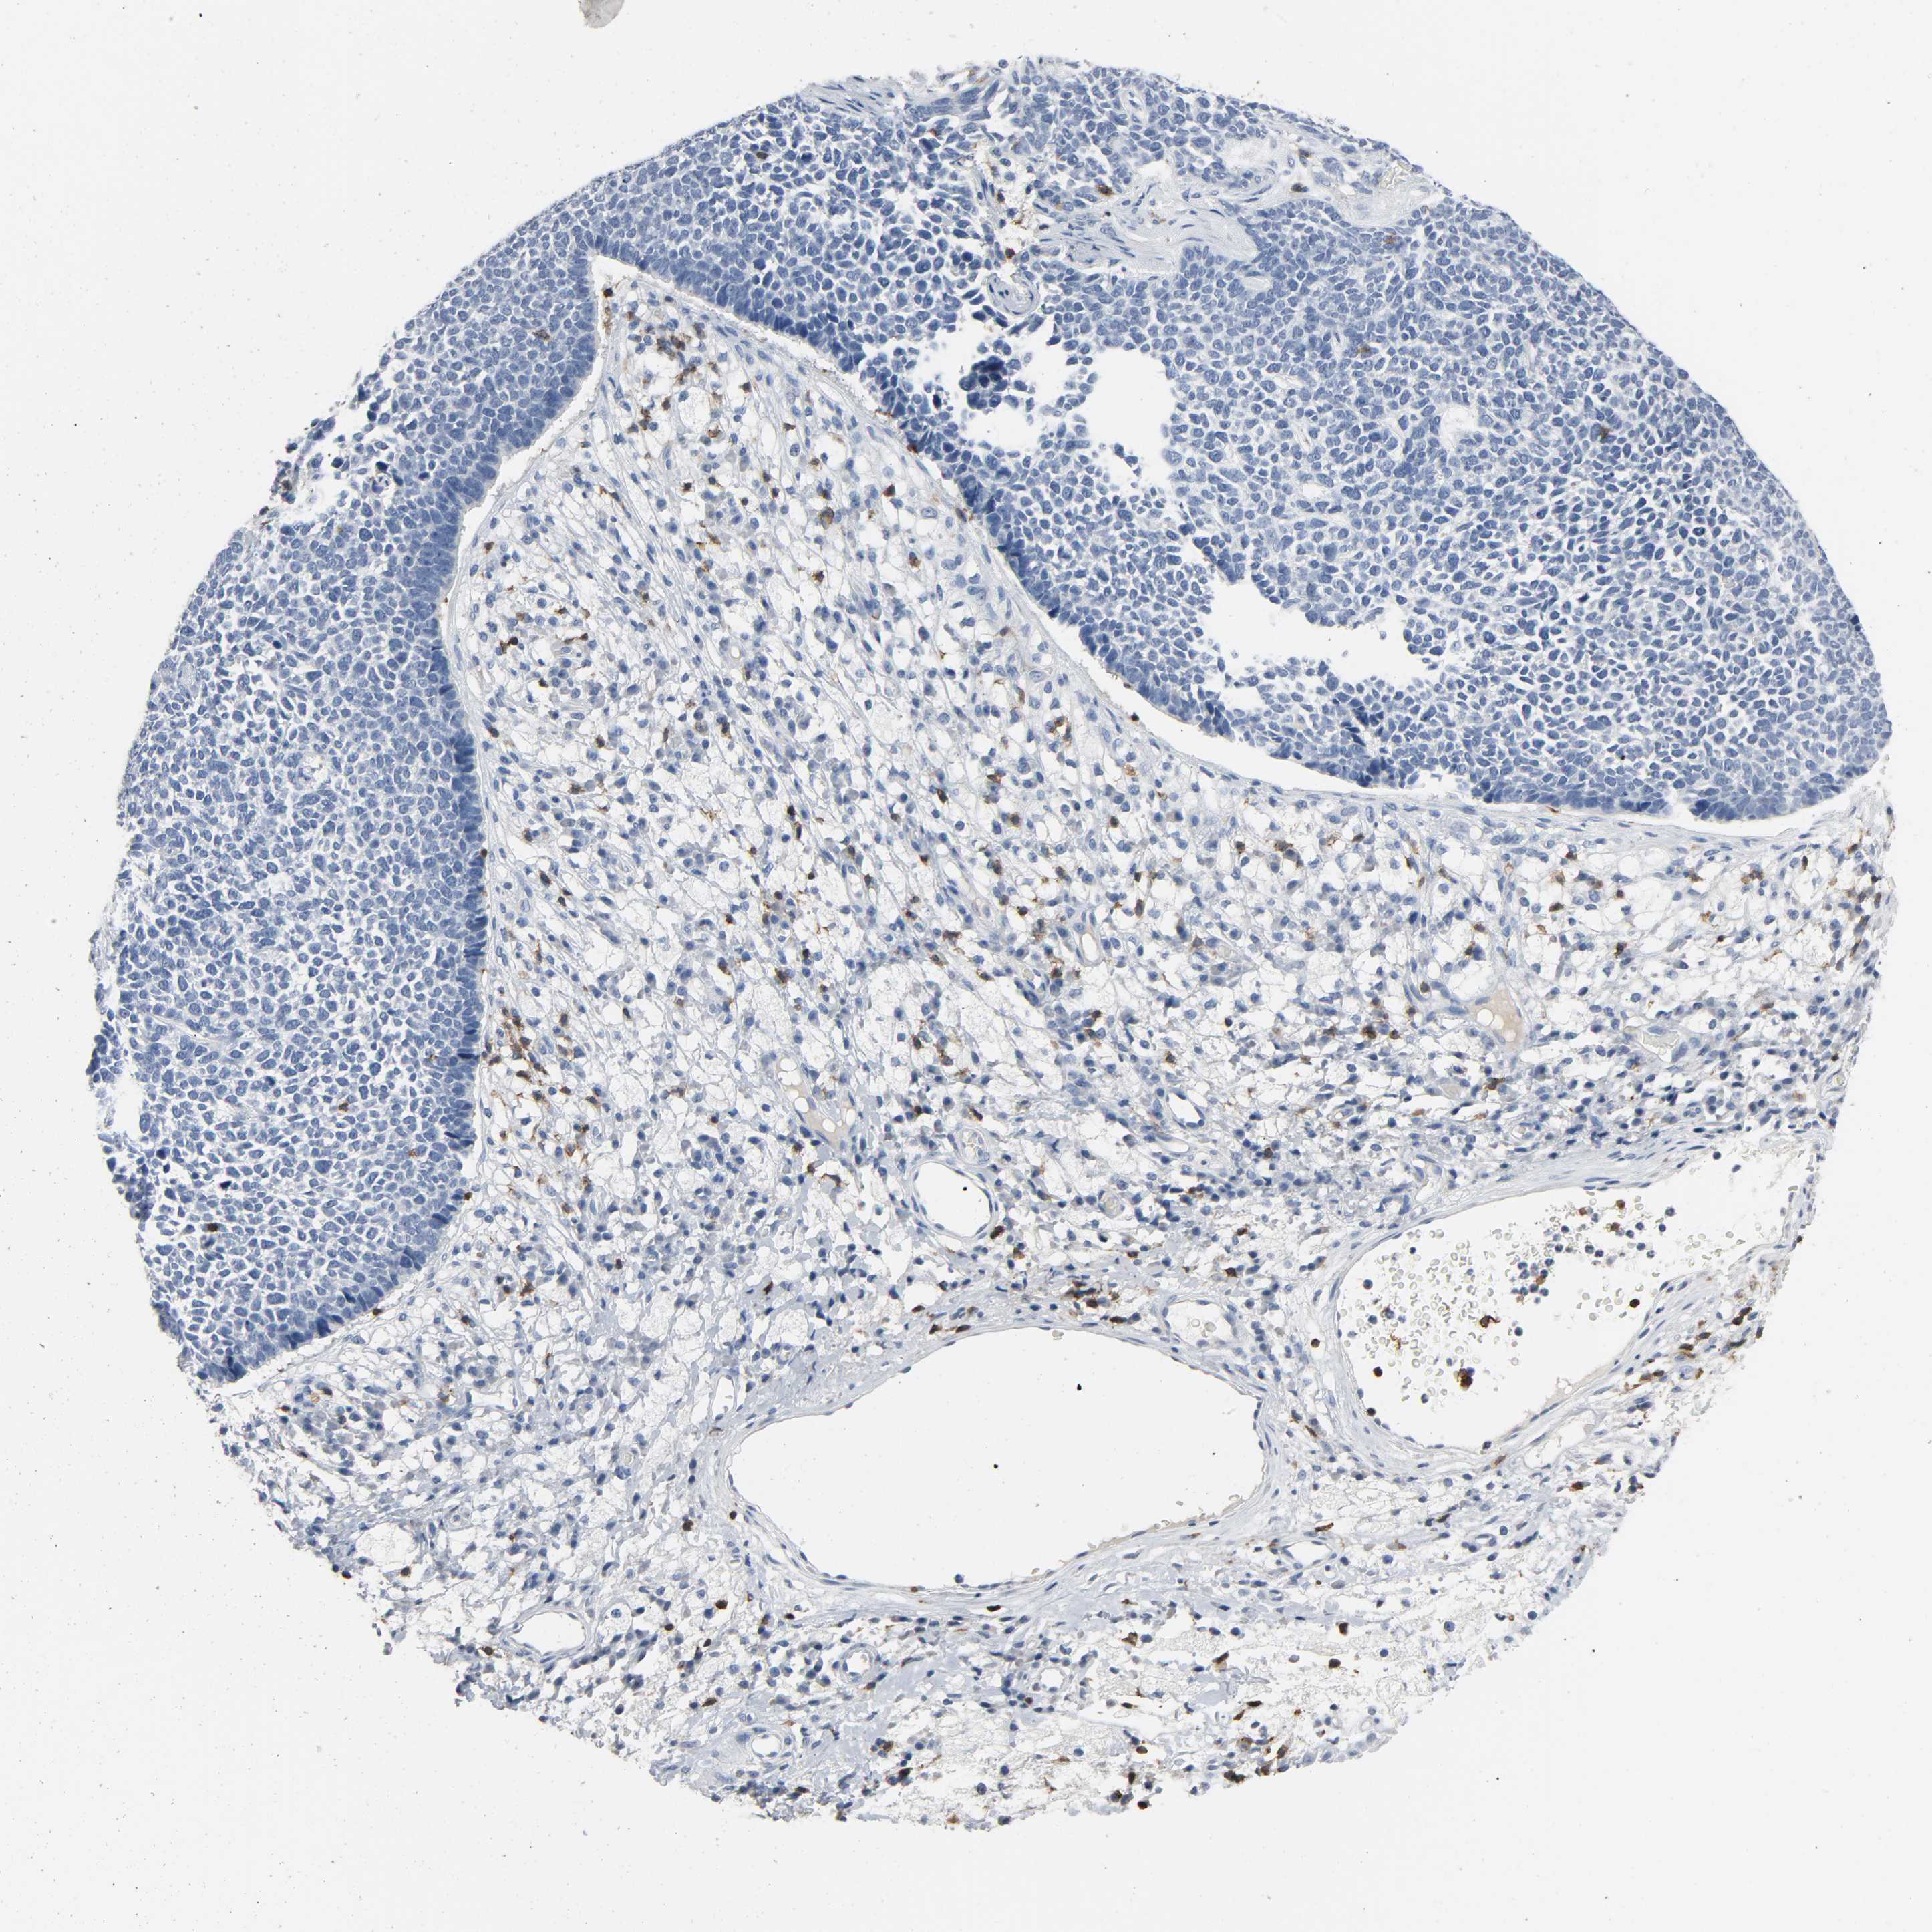

SKIN CANCER - Protein expressioni

A mouse-over function shows sample information and annotation data. Click on an image to view it in a full screen mode. Samples can be filtered based on level of antibody staining by selecting one or several of the following categories: high, medium, low and not detected. The assay and annotation is described here.

Antibody staining in the annotated cell types in the current human tissue is reported as not detected, low, medium, or high, based on conventional immunohistochemistry profiling in selected tissues. This score is based on the combination of the staining intensity and fraction of stained cells.

Each image is clickable and will lead to virtual microscopy that enables deeper exploration of all samples and also displays staining intensity scores, fraction scores and subcellular localization as well as patient and tissue information for each sample.

Antibody HPA003494

Staining

High

Medium

Low

Not detected

Intensity

Strong

Moderate

Weak

Negative

Quantity

>75%

75%-25%

<25%

None

Location

Nuclear

Cytoplasmic/membranous

Cytoplasmic/membranous,nuclear

Squamous cell carcinoma, NOS

Basal cell carcinoma